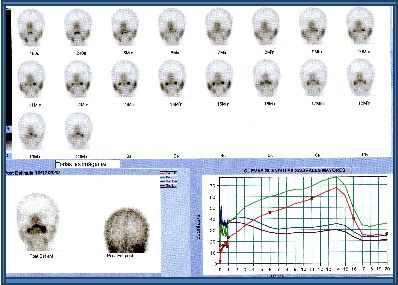

La función salival se estimó mediante la gammagrafía de glándulas salivales con administración endovenosa de 370 MBq (10 mCi) de 99mTc-pertecnetato. Los pacientes estuvieron en ayunas y fueron estudiados en posición decúbito supino, con una gammacámara de dos cabezales (Siemens E.cam, Hoffman Estates, EEUU). La adquisición fue realizada en modo dinámico en proyección AP en matriz 128x128 word a razón de 1 “frame” por minuto durante 60 minutos, incluyendo post estímulo con jugo de limón a los 15 min (21,23). Se construyeron cuatro regiones de interés ovaladas, posicionadas sobre las parótidas y submaxilares y se generaron curvas de actividad en función del tiempo (gráficas roja y verde correspondientes a las parótidas, marrón y verde a las submaxilares (21). Dependiendo de las características de captación y la excreción de las glándulas salivales, los pacientes se clasificaron en uno de cuatro patrones diferentes: Grado I, con captación y excreción normal (Fig. 1); Grado II, disfunción leve a moderada, caracterizada por disminución de la captación salival y retraso en la excreción, siendo la actividad oral igual en intensidad a la captación salival a los 60 min (Fig. 2); Grado III, disfunción moderada a severa, con marcada disminución de la captación de las glándulas salivales, excreción retardada y captación glandular mayor que la actividad oral a los 60 min; Grado IV, disfunción severa con disminución marcada de la captación glandular y la actividad de fondo más alta que la salival durante todo el estudio (22,23).